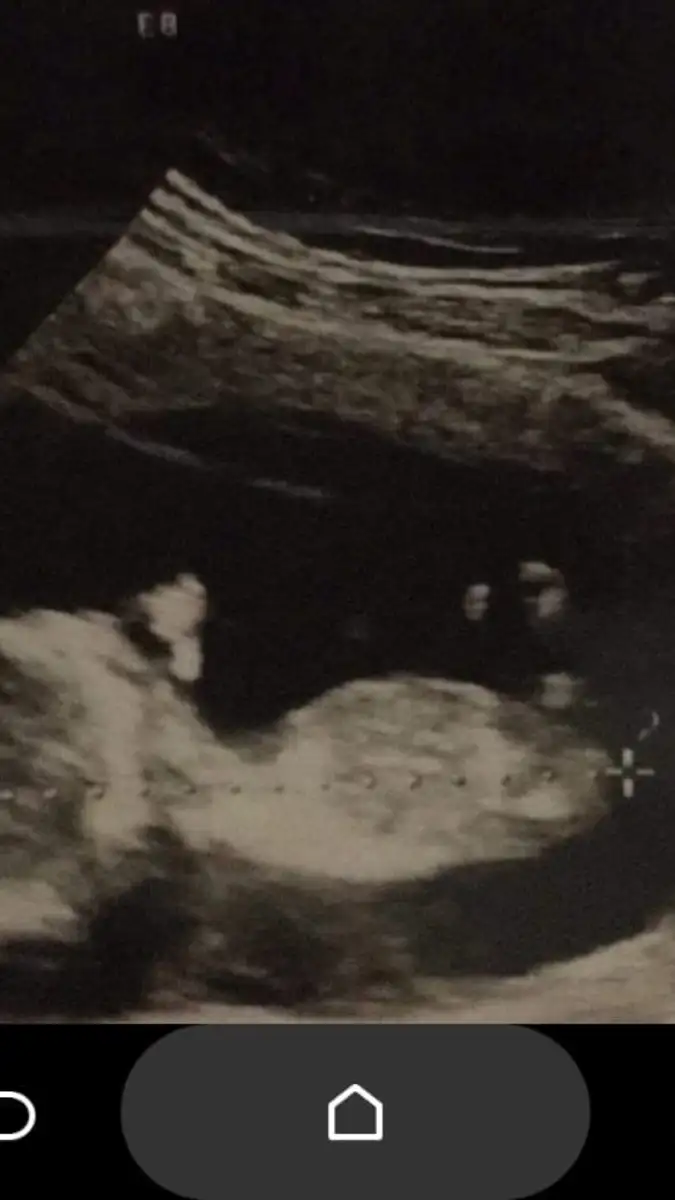

kızlar bnmkı doktr kız dedı once cıkıntısı yok dedı snra bı cıkıntı var gbı ama .Kordonda olablr bsey dyemm dedı bı bkrmısınz

Eki Görüntüle 2223272 kızlar bnmkı doktr kız dedı once cıkıntısı yok dedı snra bı cıkıntı var gbı ama .Kordonda olablr bsey dyemm dedı bı bkrmısınz

Hiç anlayamadım ultrason görüntüsünden

Ama bi çıkıntı gördüm eğer o hakikaten kordon değilse kesin erkek derdim acayip yukarı açılı duruyo